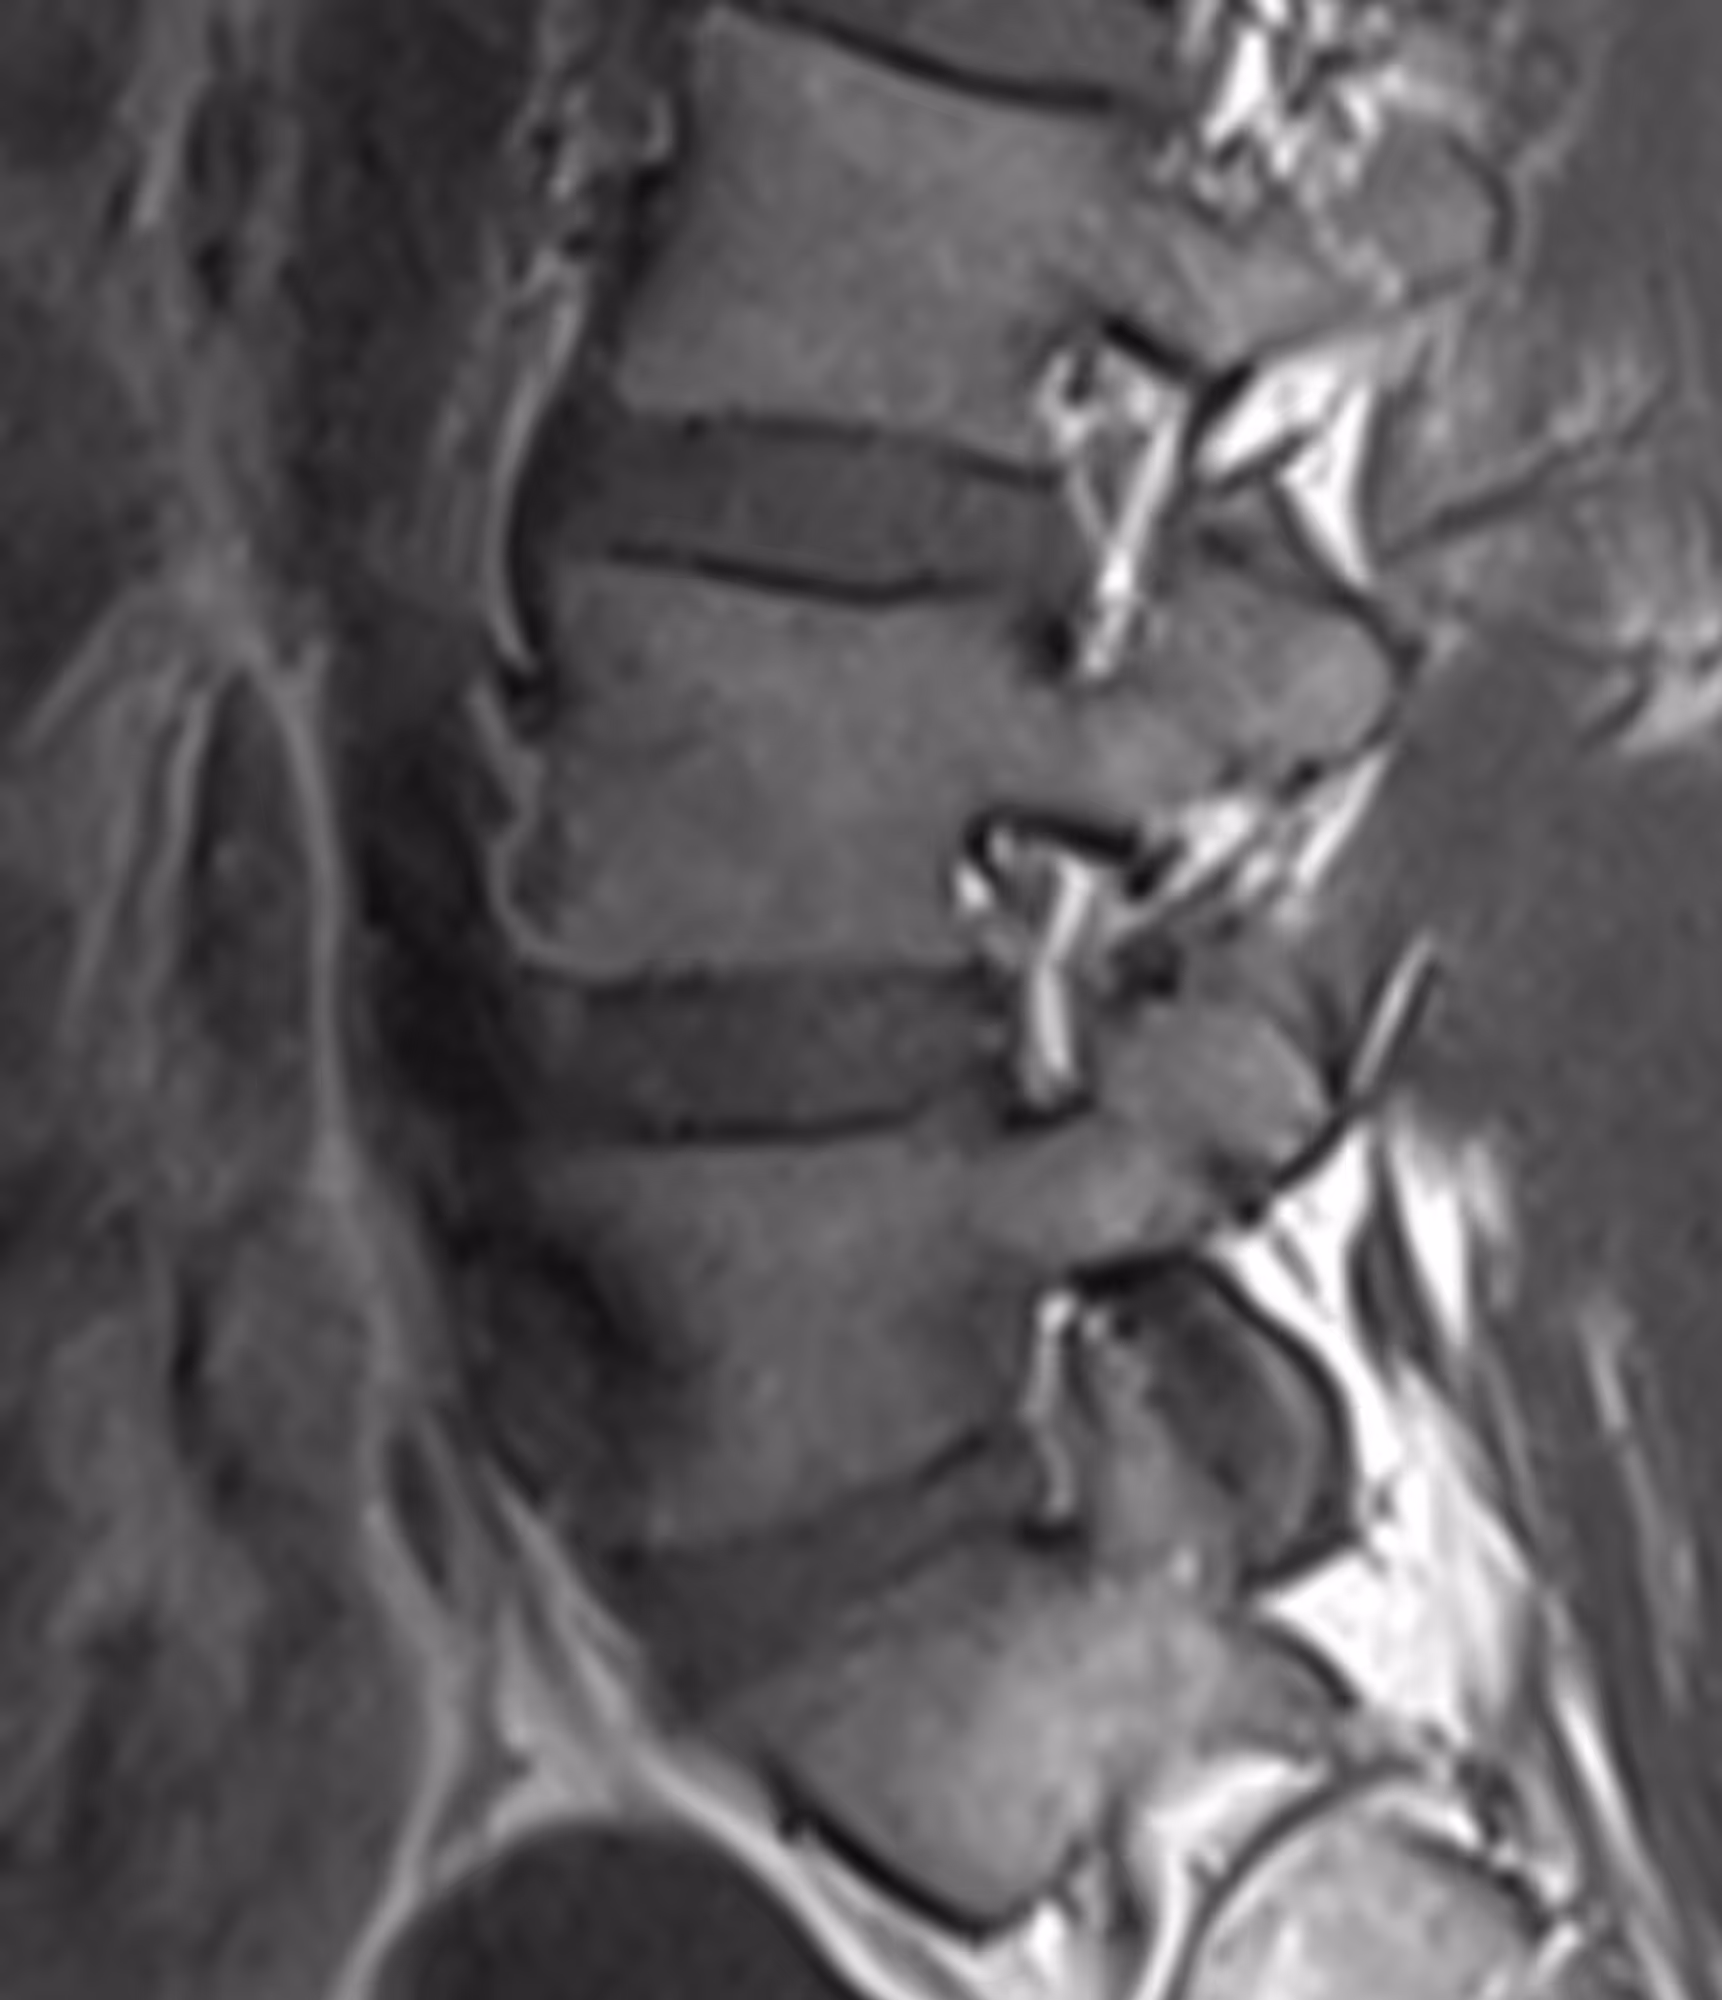

A 45-year-old female presenting with left-sided lumbosciatica, resistant to treatment.

LumbarMR revealed a foraminal disc herniation.